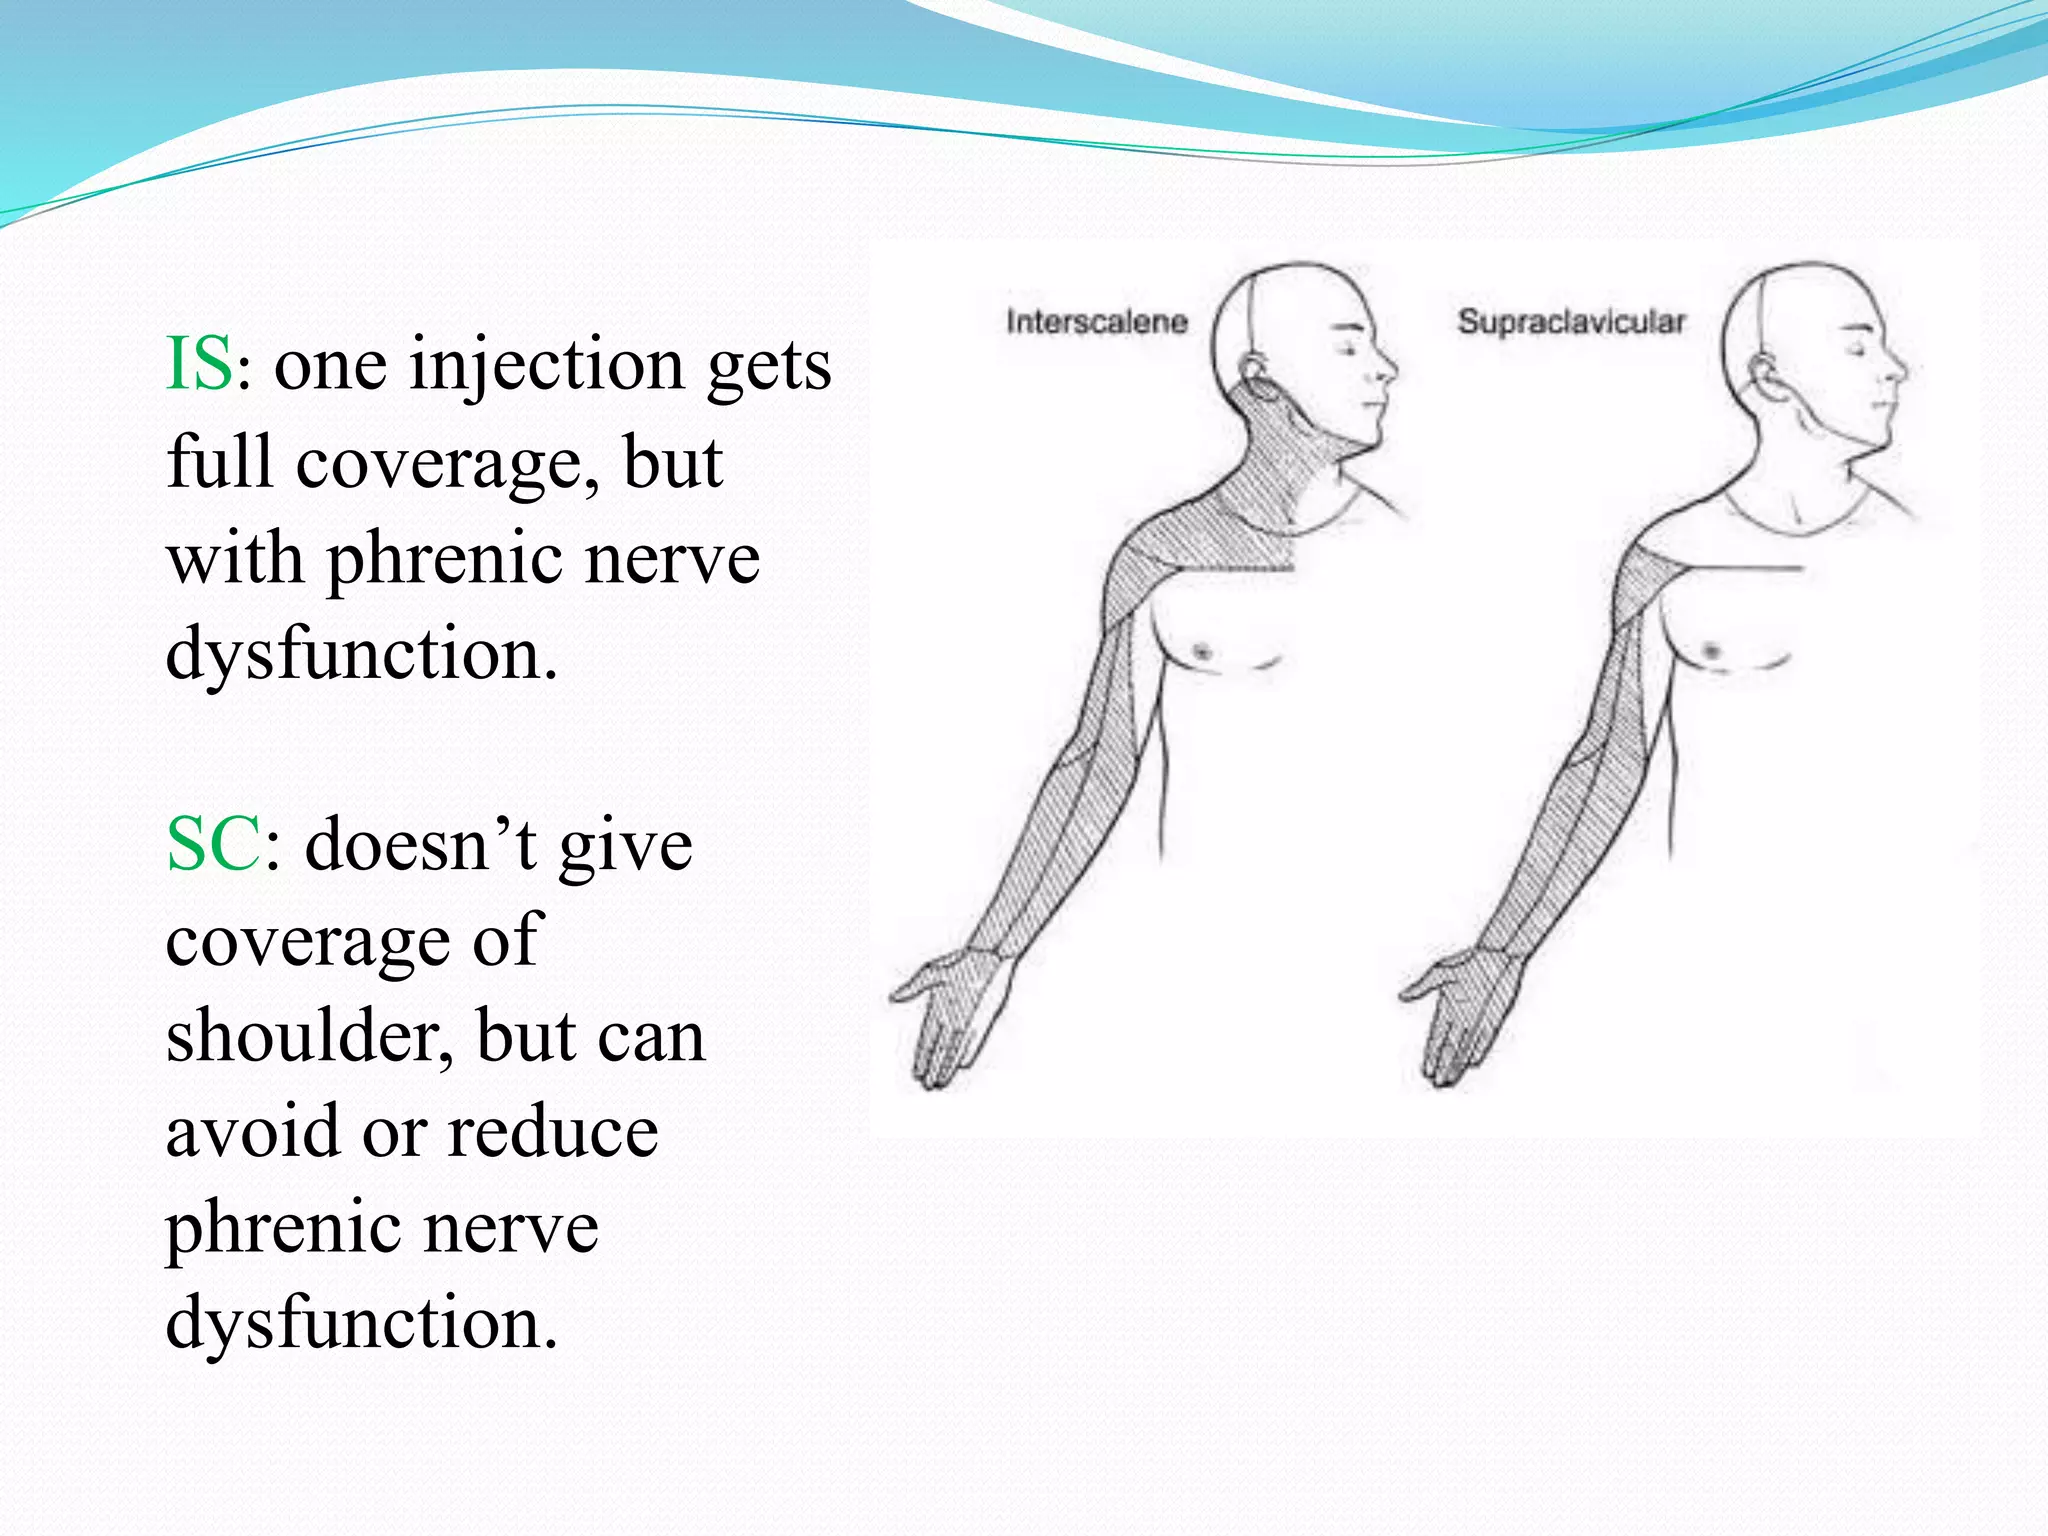

This document provides an overview of brachial plexus anatomy and techniques for brachial plexus nerve blocks. It begins with a description of the brachial plexus formation from cervical and thoracic nerve roots and its branching pattern. Four main approaches for brachial plexus nerve blocks are described: interscalene, supraclavicular, infraclavicular, and axillary. Details are provided on the anatomy and techniques for performing interscalene and supraclavicular brachial plexus blocks. Ultrasound guidance is discussed as an advancement which allows real-time visualization of needle and nerve. Complications are also summarized.